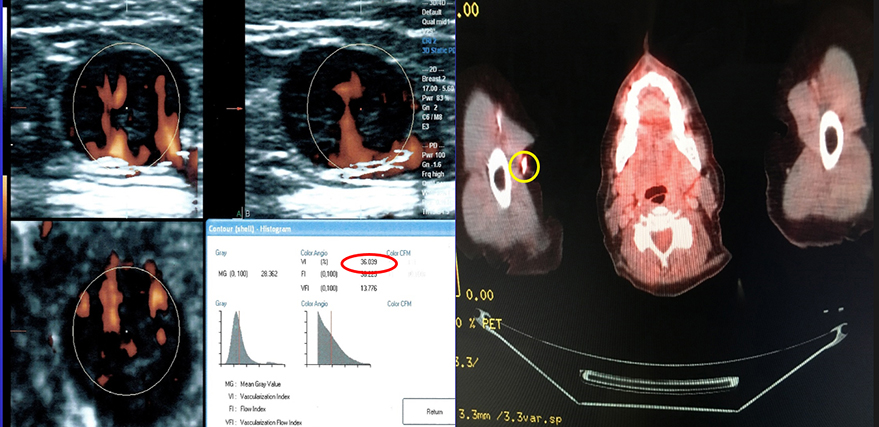

+ PET SCAN - AXILLA NODE

3 axillary nodes palpated one positive node 36% vessel density=highly aggressive

This patient had three lymph nodes. The ultrasound vessel density shows only one of the nodes is active with a 36% vessel density indicating this lymph node alone of the three that were found is highly aggressive and needs to be treated. The image on the right is the pet CT scan confirming the same. The red circle in the bottom squaredemonstrates a quantitative measure of tumor vessels. Given that you have a 36% vessel density, you can follow it weekly or monthly depending upon the treatment- to see if it's going up or down in order to adjust the treatment or completely stop the treatment to avoid unwanted side effects of the wrong therapy.